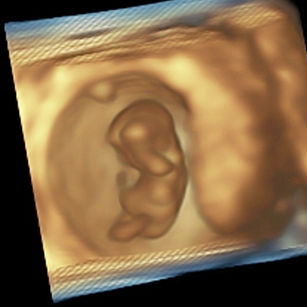

10 Weeks Pregnant

Size: ~1.2 inches (3 cm), the size of a Strawberry!

Development Highlights:

Fingers and toes separate fully.

Tail has disappeared; facial features more recognizable.